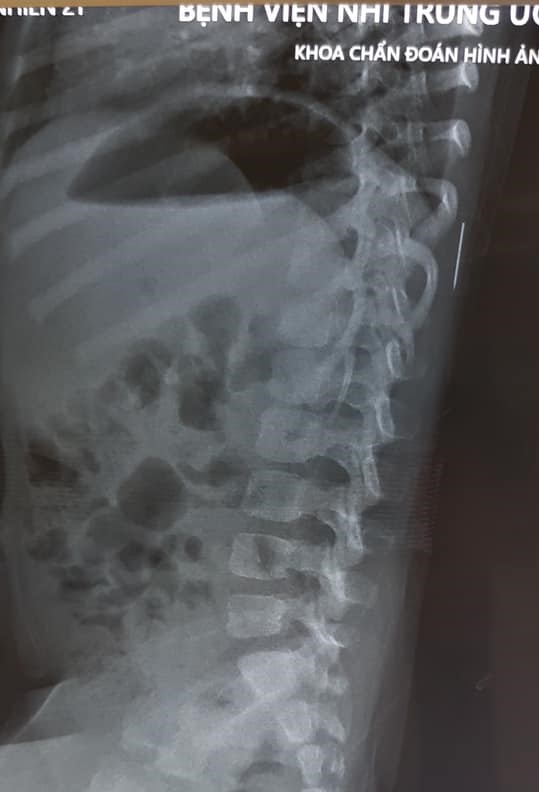

15/10/2020 20:39Bé gái 3 tuổi bị sốt cao liên tục, được đưa đi khám thì phát hiện chiếc kim khâu dài 17mm trong cột sống

Tai nạn xảy đến với bé gái H.M (3 tuổi, Phú Thọ) thời điểm nào gia đình cũng không rõ. Bố của bé M cho biết, ngày 10/10 bé lên cơn sốt 39 độ C không rõ nguyên nhân. Trước đó, cứ 2-3 ngày cháu lại bị sốt.

Tại Bệnh viện Nhi Trung ương, trong quá trình thăm khám, các bác sĩ đã tiến hành cho cháu chụp X-quang và phát hiện có dị vật trong phần mềm vùng cơ lưng trái, đốt sống 11.

Theo thạc sĩ, bác sĩ Nguyễn Vũ Hoàng, người trực tiếp phẫu thuật cho cháu M, sau khi tiến hành chụp CT dựng hình 3D lồng ngực và siêu âm thành ngực, các bác sĩ chuyên khoa Chỉnh hình Nhi và Chẩn đoán hình ảnh cùng nhau hội chẩn và chỉ định bệnh nhi cần được phẫu thuật lấy dị vật ra khỏi cơ thể. Trong quá trình mổ, để xác định chính xác vị trí dị vật, các bác sĩ lại tiếp tục tiến hành siêu âm trong mổ và chụp C-Arm.